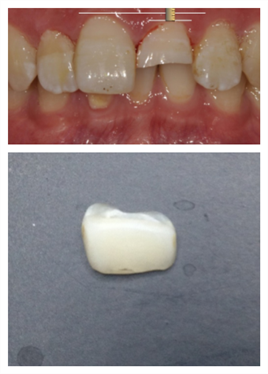

患者男,12岁,21牙外伤折断露髓,进行根管治疗后用树脂材料直接将碎片与剩余牙体组织粘接。 此方法虽能够最大限度的保留牙体组织,但也存在一定局限性,例如牙体变色,碎片再脱落,不能承受过大咬合负荷。